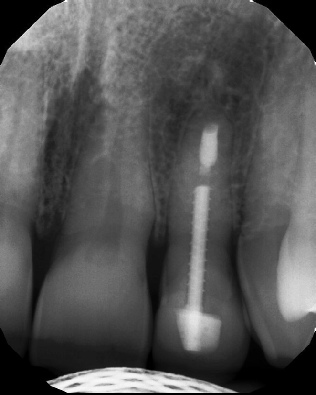

Apicoectomy - Surgical Root Canal Pre-op (post trauma) Coronal segments obturated Apical segments surgically removed 3 years